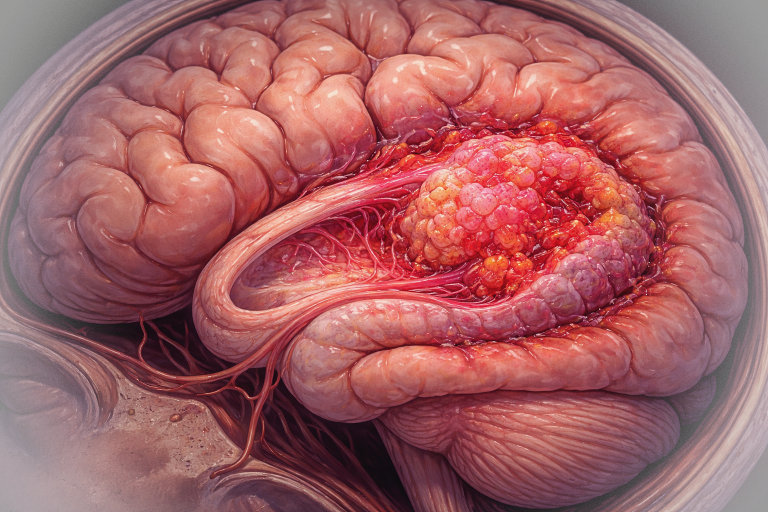

Tumorile glioneuronale sunt neoplasme rare ale sistemului nervos central (SNC), care combină elemente neuronale și gliale în proporții variabile. Aceste tumori se disting de tumorile pur gliale (precum astrocitoamele sau oligodendrogliomele) prin prezența unei componente neuronale diferențiate. De obicei, sunt tumori de grad scăzut, cu evoluție lentă, dar unele pot prezenta comportament agresiv. Majoritatea apar la copii, adolescenți și adulți tineri, fiind asociate frecvent cu epilepsie.

- Localizare: Lobi temporali, frecvent implicând cortexul cerebral.

- Histologie: Prezența de neuroni maturi atipici și celule gliale. Poate prezenta mutația BRAF V600E.

- Imagistică prin RMN: Aspecte caracteristice (leziuni corticale, fără edem semnificativ, fără contrast intens).

- Histopatologie: Prezența celulelor neuronale și gliale.